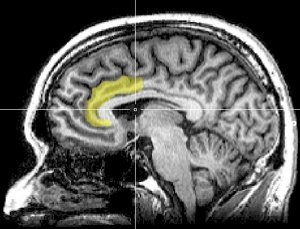

Para tratar de responder a estas preguntas nos vamos a referir a los estudios que abordan la misma problemática refiriéndose a la dicotomía liberales/conservadores, no coincidente con la de izquierda/derecha, pues de esta última no conocemos estudios científicos relacionados con el cerebro1. En 2007, un equipo de investigadores de las universidades de Nueva York y California realizó un trabajo experimental, publicado en la prestigiosa revista Nature Neuroscience, que mostró, mediante potenciales eléctricos evocados e imágenes de resonancia magnética funcional, que en situaciones de conflicto las personas políticamente liberales presentan más actividad que las políticamente conservadoras en la circunvolución cingulada anterior, una región del lóbulo temporal del cerebro caracterizada, entre otras funciones, por responder, cual alarma biológica, a situaciones en las que lo que razonamos no coincide con lo que sentimos.

De ese modo, los investigadores concluyeron que frente a las situaciones nuevas que requieren modificar los comportamientos habituales los liberales tienen más sensibilidad neurocognitiva que los conservadores. Asimismo, de esos datos dedujeron que la menor sensibilidad neurocognitiva de los conservadores en tales situaciones podría explicar su más estructurado y persistente comportamiento. La valoración neurofisiológica de este estudio fue tan consistente que sirvió para predecir con bastante acierto si los participantes habían votado a John Kerry o a George Bush en la elección norteamericana de 2014. Repare el lector, porque es importante, en que los autores de este trabajo al hablar de sensibilidad neurocognitiva no se refieren a un tipo de sensibilidad moralmente enjuiciable, sino a un modo fisiológico de funcionamiento del cerebro.

Posteriormente, en 2011, un estudio de investigadores del University College de Londres, también con neuroimágenes de resonancia magnética, mostró que los liberales tenían un mayor volumen de sustancia gris, es decir, de neuronas, en dicha región cerebral, la circunvolución cingulada anterior, mientras que los conservadores superaban a los liberales en el volumen de esa misma sustancia en la amígdala, una estructura del cerebro emocional. No obstante, falta determinar si esas diferencias cerebrales son o no las causantes de las orientaciones políticas de las personas.

Neuroimagen sagital del cerebro humano mostrando en color amarillo la circunvolución cingulada anterior, un área que ha sido relacionada con la orientación ideológica de las personas. GEOFF B HALL